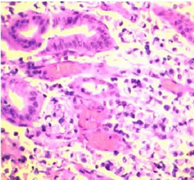

肛门指诊:肛门周围皮肤完整,无破溃、化脓、红肿等,齿状线上5 cm处于后壁触及菜花样肿物,肿物约占直肠管壁2/3周,质韧,表面不光滑,为菜花样,活动度差,无明显触痛,未能触及肿物上缘.退指套染血为暗红色。血清学检查:癌胚抗原(CEA)4.3 ng/ml(<5.0 ng/m1),糖抗原199(CAl99)99.1U/ml(<37.0 U/m1),CAl5310.7U/ml(<31.0U/m1)。磁共振成像(MRI):直肠癌、突破浆膜面,直肠窝及盆壁淋巴结转移。病理结果:(直肠)低分化黏液腺癌,部分细胞为印戒细胞(图1A)。